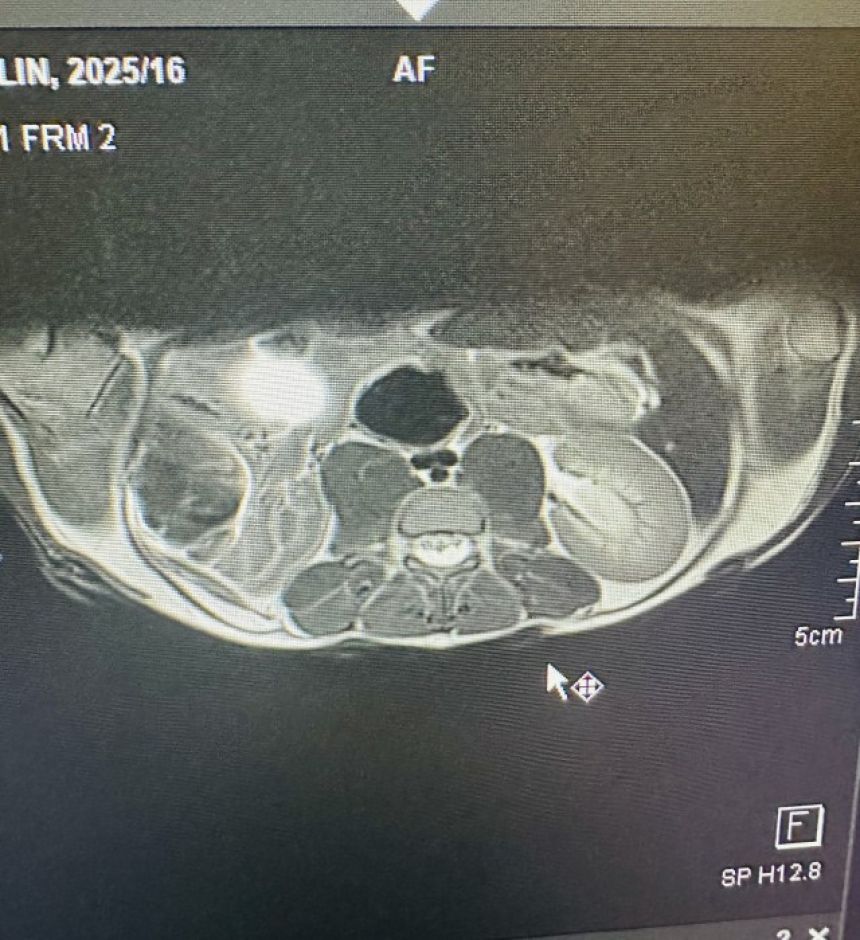

この画像を大きなサイズで見る脊髄に感染症が確認された

この病院で、センザンコウのMRI検査が行われたのはこれが初めてだった。しかし他に選択肢はなく、この「賭け」は報われることになる。

最初のMRI検査で、ヘリテージには重度の脊髄膿瘍と脂肪組織炎が確認された。エマさんは、検査結果についてこう説明する。

センザンコウでこのような症状はこれまで見たことがありません。なぜこんなことが起きたのか、100%確信は持てませんが、密猟がこの事態に拍車をかけたことだけは確かです

4週間後に実施された2回目のMRI検査では、症状に大幅な改善が認められたものの、まだいくつかの懸念事項が残っていた。

この画像を大きなサイズで見るヘリテージの症例は非常に稀なものだったため、治療は「暗闇の中で作業する」ようなものだったという。

彼女は病院から、もっと落ち着いて過ごせるエマさんのセンターへと移され、抗生物質の点滴と、抗炎症剤の投与による治療が続けられた。

そして2か月にわたる集中治療が続けられた結果、12月4日に行われた3回目のMRI検査で、患部の完全な消失が確認されたのだ。